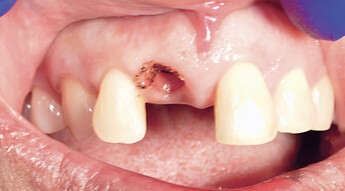

A temporary appliance was delivered and the site allowed to heal. After approximately three months, the healing abutment was removed and stability was checked with a Penguin RFA® A small amount of gingival recontouring was completed with a diode laser, and impressions were taken. The final BruxZir® Esthetic restoration was delivered, and final adjustments were made.